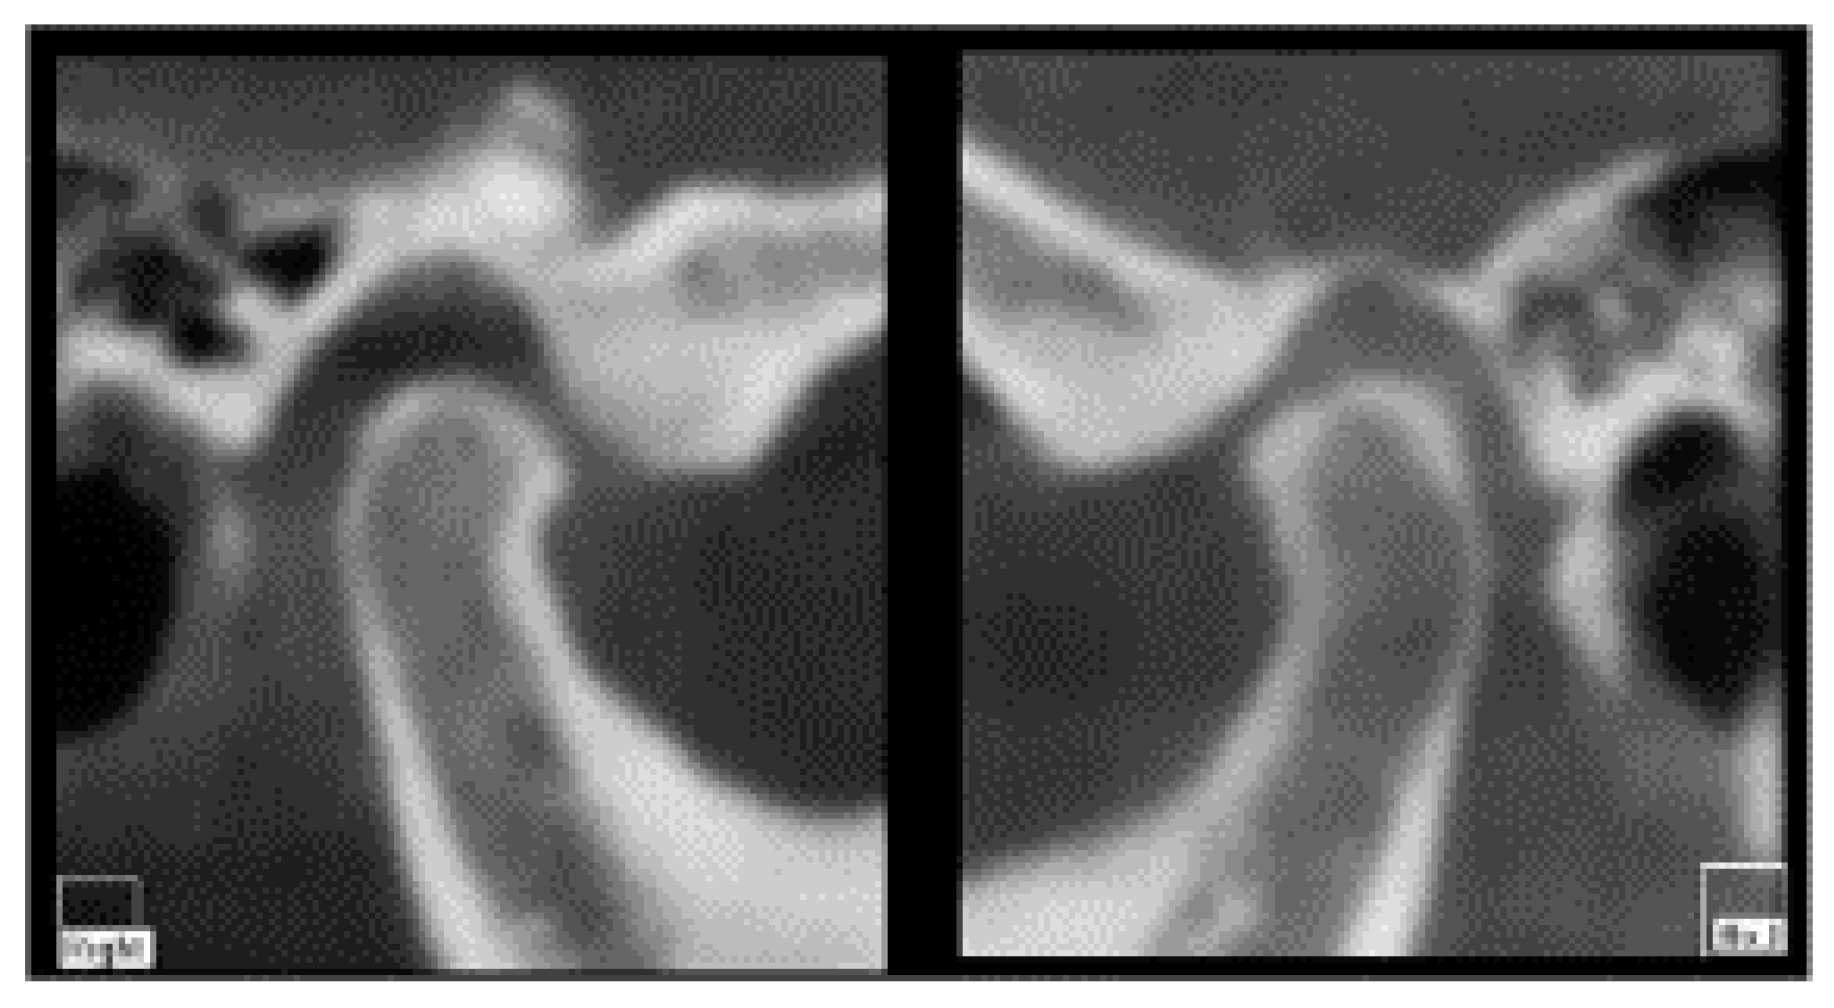

The patient showed a small opening width, approximately 25–30 mm, without pain. Lateral movements were within the norm. MRI images of the TMJ show anterior displacement of the disc with reduction (Figure 27).

Figure 27. MRI images with a closed and open mouth.